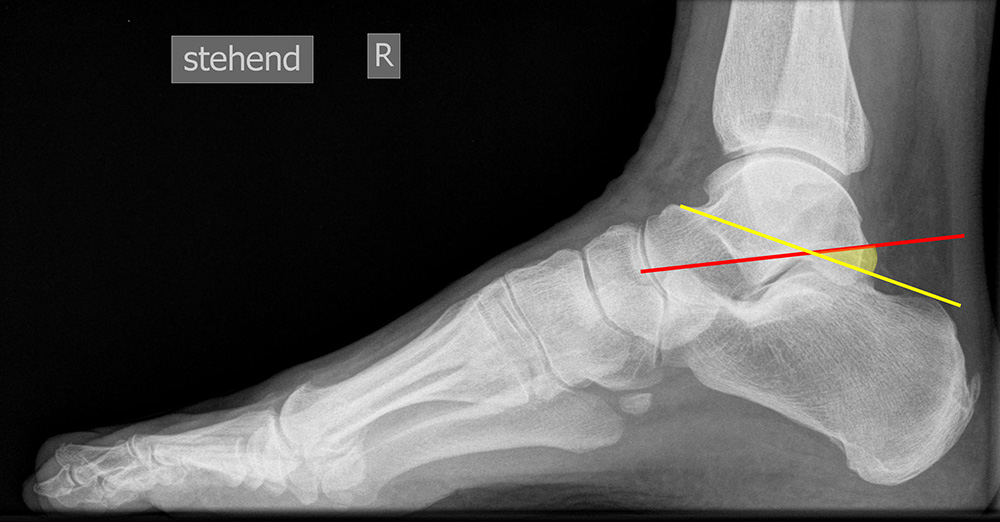

Beurteilung von Fehlstellungen des Mittel- und Rückfußes

Zur Vollansicht und zum Lesen der Bildbeschreibung bitte die Bilder anklicken.

Achsen auf der lateralen Aufnahme

Die Grundlinie (blau) ist definiert durch den tiefsten Punkt der Sesambeine und den tiefsten Punkt des Kalkaneus.

CPA (Calcaneal pitch angle): Der Kalkaneus Inklinationswinkel liegt zwischen der Grundlinie (blau) und der plantaren Begrenzung des Kalkaneus (grün) (Norm 20,8 ± 4,1° 11, 15-39° (Zwipp 2014)).

LTCA (Lateral talocalcaneal angle): Der laterale talokalkaneare Winkel liegt wird gebildet aus der Talusachse (türkis) und einer Verbindungslinie zwischen dem Oberrand des Proc. ant. Calcanei und der dorsalen Begrenzung des Kalkaneus (gelb). (Norm: 33° Range 25-45°) 1213).

LTMA (Lateral talometatarsal angle, Syn. Meary’s angle): Der laterale talometatarsale Winkel wird gebildet aus der Achse des Os metatarsale I (rot) und der Achse des Talus (türkis). (Norm: 7,1 ± 10,8 11).

Böhler-Winkel (Syn. Tubergelenkwinkel)

Es wird eine Linie vom Proc. ant. calcanei zur dorsalen Facette des Subtalargelenks gezogen (rot). Die zweite Linie verläuft von der kranialen Begrenzung des Tuber calcanei zum Subtalargelenk (gelb). Gemessen wird der nach dorsal offene Winkel zwischen den beiden Linien (Norm: 22-48° 9).

Meary’s angle dorsoplantar (Talo-Metatarsale-I-Winkel)

Der Talo-Metatarsale-I-Winkel wird auf den belasteten dorsoplantaren und lateralen Aufnahmen bestimmt. Es wird jeweils die Achse durch den Talushals gelegt (grün) und der Winkel zur Achse des Os metatarsale I bestimmt (rot). Der Winkel liefert keine Information darüber, an welcher Stelle sich die Fehlstellung befindet. Auch kann ein Serpentinen-Fuß „physiologische“ Werte liefern, da Os metatarsale I und Talushals parallele Achsen aufweisen, obwohl eine erhebliche Fehlstellung vorliegt 11. (Norm: 7,7 ± 8,2° 11).

Meary’s angle lateral (Talo-Metatarsale-I-Winkel)

Der Talo-Metatarsale-I-Winkel wird auf den belasteten dorsoplantaren und lateralen Aufnahmen bestimmt. Es wird jeweils die Achse durch den Talushals gelegt (grün) und der Winkel zur Achse des Os metatarsale I bestimmt (rot). Der Winkel liefert keine Information darüber, an welcher Stelle sich die Fehlstellung befindet. Die Fehlstellung kann das Talonaviculare-Gelenk (TN-Gelenks), das Naviculocuneiforme-Gelenk (NC-Gelenks) oder des Tarsometatarsale-I-Gelenk (TMT-I-Gelenks) betreffen, bzw. auch mehrere Gelenke einbeziehen. Der Talo-Metatarsale-I-Winkel gilt als zuverlässigster Parameter in der Differenzierung symptomatischer Pes planovalgus-Deformitäten gegenüber einer Kontrollgruppe 11.  (Norm: 7,1 ± 10,8 11).